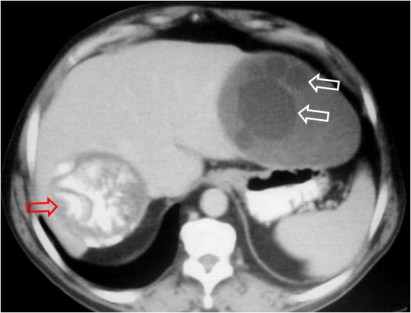

SIGNO DE LA VESÍCULA HIJA

En el quiste hidatídico hepático y otros órganos abdominales, la presencia de vesículas hijas (quistes dentro del quiste) puede verse tanto en la ecografía como en el TC (flechas blancas) y en resonancia magnética. Además del quiste del lóbulo hepático izquierdo, que muestra el signo, hay otro quiste hidatídico con pared calcificada en el lóbulo hepático derecho (flecha roja).